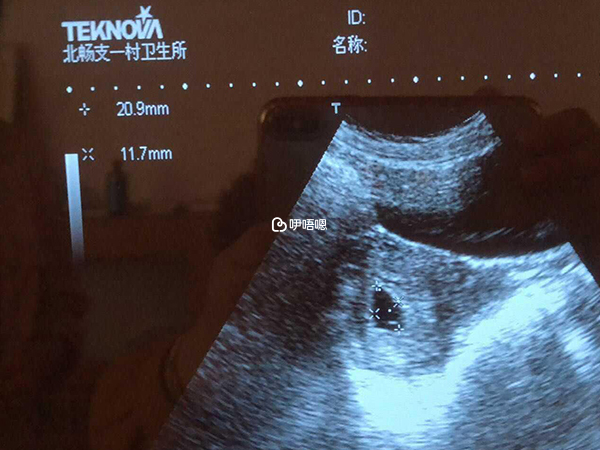

胎囊檢查是胎囊得橫截面以及胎芽的資料,通過這兩個資料可以看生男孩還是生女孩,通過胎囊橫截面看男女,對於資料檢查的時間也是有要求的,一般必須要8周以內的時間,其中最好的是懷孕40-50天的結果,此時是最準的。

除了橫截面觀察資料之外,最好是有B超圖片,此時除了觀察胎囊的情況之外,還要看到胎芽的資料,結合起來更好判斷,對於結果的分析也會更加準確。

在懷孕2個月的時候,胎囊的大小大概在4釐米左右,胎芽一般在2釐米左右,但這個只是參考值,孕婦胎囊大小和受孕時間早晚以及孕婦營養、基因有直接聯絡,根據已生男孩寶媽的經驗總結,每個B超師做B超的時候,截面會擷取的方位不一樣,有的橫截面,有的擷取豎截面。

懷孕2個月男孩胎囊B超資料中,如果前兩個資料是第三個資料的兩倍以上,比如:21*21*10這樣懷男孩機率大,如果三個資料都比較接近,比如:37*28*23這樣懷女孩可能性大,這兩種情況下的資料不用看影象也可以分辨出懷男孩女孩。

如果胎囊後兩個資料幾乎一樣,而第一個資料值最大,那麼通過孕囊大小看男女的方法結合例項,比如25*16*16mm,雖然沒有成倍數關係,但這樣的資料是男孩的機率有80%。